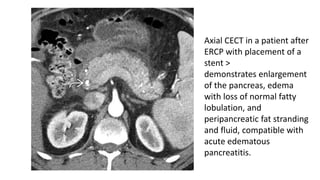

Axial CECT in a patient after

ERCP with placement of a

stent >

demonstrates enlargement

of the pancreas, edema

with loss of normal fatty

lobulation, and

peripancreatic fat stranding

and fluid, compatible with

acute edematous

pancreatitis.